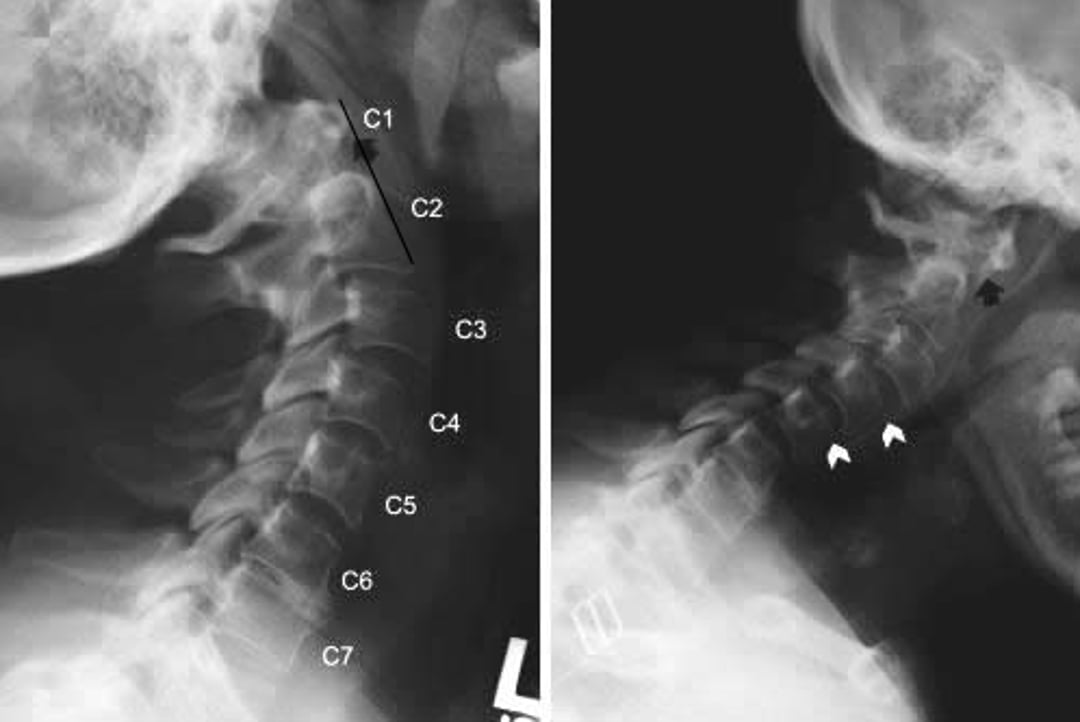

環軸関節亜脱臼

関節リウマチの患者に生じた環軸関節亜脱臼と軸椎下亜脱臼を示した頸椎X線写真である。頸部伸展位(左)および屈曲位(右)で頸椎の側面像が撮影されている。屈曲位では,C1の前弓がC2の歯突起(黒矢印の後方)よりもはるか前方に位置し,前方への亜脱臼を示す。この所見は伸展位では明らかではなく(黒矢印),環軸椎亜脱臼が動的であることが示唆される。軸椎下のずれ(subaxial translation)(白矢頭)も伸展位のC2-C3およびC3-C4ならびに屈曲位のC3-C4およびC4-C5にみられる。